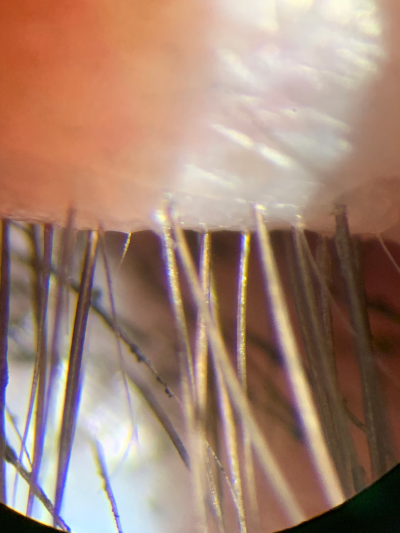

Here is a real life example of a a successful treatment for a lid condition, the patient, a contact lens wearer, had found lenses becoming increasing uncomfortable over years, even having to attend an eye hospital while abroad, trying many different dry eye drops or having new lenses prescribed didn't help. Below are images taken before and after specific treatment that not only resolved the lid appearance but solved the contact lens discomfort problems as well.

| superior lid and lashes 16 March 2019 |

superior lid and lashes, 13 April 2019 |